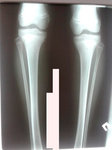

Рентген перед снятием аппаратов.

IMG_3589-12-06-19-11-49.JPG

IMG_3590-12-06-19-11-49.JPG